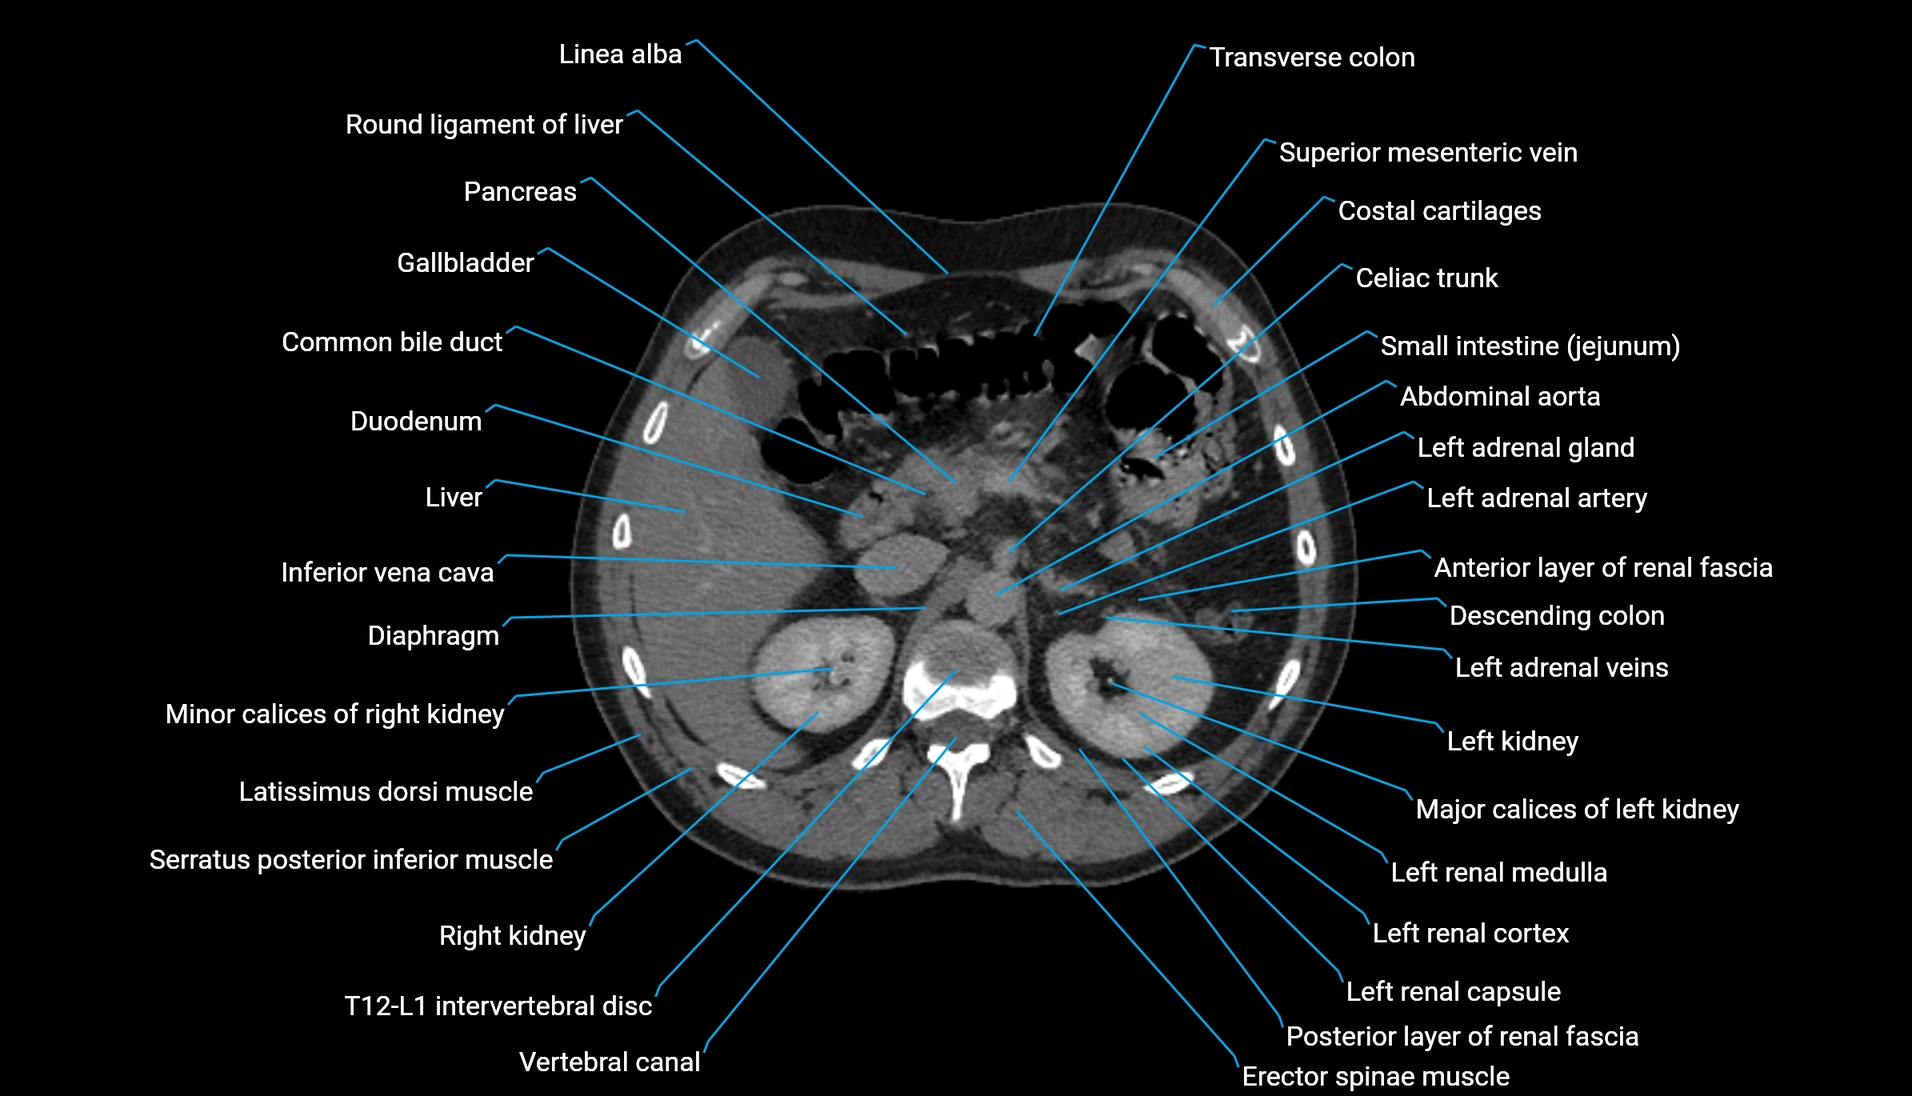

CT Appearance

Non-contrast CT:

-

Demonstrates cortical bone of acetabular rim in excellent detail

Detects fractures, dysplasia, retroversion, or bony overcoverage (pincer impingement)

3D reconstructions used in preoperative hip surgery planning

CT VRT 3D image

CT image